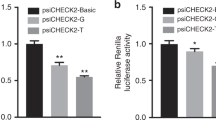

Recent studies have reported that several microRNAs (miRNAs) play pivotal roles in cardiac development under hypoxic intrauterine environment, being termed as hypoxia-responsive miRNAs (Azzouzi et al. 2015; Lock et al. 2017). Such miRNAs, as miR-199a and miR-210, presented a significant correlation with cardiac energy metabolism. Rane et al. 2009 suggested that miR-199a, is a miRNA downregulated under hypoxia, regulated cardiac metabolism by targetting hypoxia-inducible factor-1 alpha and sirtuin 1. Hu et al. 2010 reported that upregulated hypoxia-responsive miR-210 exhibits a cardio-protective effect by inhibiting Efna3 and Ptp1b, in a mouse model of myocardial infarction. Besides, it is widely reported that miR-124 is a downregulated hypoxia-responsive miRNA involved in the regulation of biological processes in a variety of cells (Gong et al. 2017; Gu et al. 2016; Li et al. 2017). Moreover, a line of evidence has demonstrated that rs531564 (G>C), a functional SNP of the primary miR-124 (pri-miR-124) sequence, is associated with the expression of mature miR-124. The G allele carriers, which represent the major population, have a higher expression level of miR-124 transcript than the C allele carriers, which represent a minor population (Chen et al. 2018; Li et al. 2017; Zou et al. 2017). The rs531564 polymorphism of pri-miR-124 is also one of the risk factors for human cervical cancer, esophageal squamous cell carcinoma, colorectal cancer, and type 2 diabetes (Gao et al. 2015; Li et al. 2015; Wu and Zhang 2014; Ye et al. 2008). The downregulated miR-124 also exhibits a cardio-protective function by attenuating endoplasmic reticulum stress (Bao et al. 2017). However, evidence supporting a correlation between the rs531564 polymorphism of pri-miR-124 and CHD is inadequate.

Correlation between the rs531564 SNP and the susceptibility to CHD

The genotypes of rs531564 were in HWE in the control groups, both separately from Beijing or Gansu, and the combined control group (P = 0.16, P = 0.78, and P = 0.51, respectively) (Fig. 3). To explore the correlation between rs531564 and CHD susceptibility, both allelic and genotypic distribution were assessed. Additionally, various genetic models were applied with the adjustment for age and gender under unconditional logistic regression analyses (Table 3). The combined group data indicated that the C allele of rs531564 of pri-miR-124 is associated with the decreased risk of CHD (OR = 0.72, 95% CI = 0.55–0.93, P = 0.01). In addition, similar results were obtained by analyzing the data with other models including the following: the codominant model (OR = 0.69, 95% CI = 0.51–0.93, P = 0.03), dominant model (OR = 0.67, 95% CI = 0.50–0.91, P = 0.01), overdominant model (OR = 0.70, 95% CI = 0.52–0.95, P = 0.02), and log-additive model (OR = 0.70, 95% CI = 0.53–0.91, P = 0.01) after adjustment. In the Beijing group, the genotype distribution of rs531564 was significantly different between CHD patients and healthy controls. Our finding indicated that minor C allele was significantly associated with the decreased risk of CHD in the Beijing group. This result was consistent among the analysis with different models including the allelic model (OR = 0.36, 95% CI = 0.21–0.63, P = 3e−04), the codominant model (OR = 0.30, 95% CI = 0.16–0.56, P = 4e−04), the dominant model (OR = 0.30, 95% CI = 0.16–0.56, P = 1e−04), the overdominant model (OR = 0.30, 95% CI = 0.16–0.57, P = 1e−04), and the log-additive model (OR = 0.33, 95% CI = 0.19–0.60, P = 1e−04). However, our findings did not support a significant correlation between rs531564 SNP and the risk of CHD in the Gansu group. In addition, it was noticed that the C allele frequency in the Gansu group was higher than that in the Beijing group in both the case-only group (0.15 and 0.08, respectively, χ2 = 8.38; P = 0.0038) and overall population (0.16 and 0.14, respectively, χ2 = 1.60; P = 0.21), while it is lower in the Gansu group than that in the Beijing group if the analysis was done in the control-only group (0.17 and 0.19, respectively, χ2 = 0.61; P = 0.43).

It is critical for healthy heart development in a hypoxic intrauterine environment during early fetal life, but long-term exposure to the hypoxic environment may lead to fetal intrauterine growth restriction (Bae et al. 2003; Gagnon 2003; Herrera et al. 2016; Yue and Tomanek 1999). Chronic intrauterine hypoxia also affects heart development at some stages, and possible molecular mechanisms include that chronic fetal hypoxia alters cardiac gene expression, accelerates pre-existing cardiomyocytes exit the cell cycle, increases myocyte apoptosis, and reduces in the number of cardiomyocytes (Botting et al. 2014; Osterman et al. 2015; Zhang 2005). Furthermore, studies have shown that the incidence rate and the severity of CHD are higher in high-altitude areas. Hypoxic environment was considered as a risk factor of congenital heart disease in high-altitude areas (Hasan 2016; Miao et al. 1988; Zheng et al. 2013). As mentioned above, miR-124 is involved in the regulation of cardiomyocyte metabolism under hypoxic conditions. Moreover, it is widely reported that the G allele of rs531564, in pri-miR-124, is associated with increased mature miR-124 expression (Chen et al. 2018; Li et al. 2017; Zou et al. 2017). In this study, we evaluated the association between the rs531564 polymorphism of pri-miR-124 and CHD in two independent groups of Chinese patients who were from Beijing (with altitudes ranging from 28 to 96 m) or Gansu (with altitudes ranging from 1085 to 2690 m). Our findings revealed that the C allele of rs531564 of pri-miR-124 is associated with the decreased risk of CHD, especially complex CHD, in the group from Beijing, but not in the Gansu group. The correlation between the different geographical areas and CHD risk is different for the rs531564 SNP in this study. It seems to be consistent with the report that the etiology of sporadic, non-syndromic CHD involves the interaction of multiple genetic and environmental factors (Hinton 2013). The decrease risk of CHD risk associated with the C allele of rs531564 may be partly explained by the lower expression level of mature miR-124 than that of the G allele. Low levels of miR-124 expression contribute to the maintenance of cardiomyocyte metabolism under hypoxic conditions caused by placental insufficiency or hypoxic environmental exposure. Additionally, we noticed that although there was no statistical correlation between the C allele and CHD in the tested patients from Gansu, where the altitude is high, the C allele frequency in the Gansu group was higher than that in the Beijing group in the case-only group or overall population. These data indicated that the higher frequency of the C allele in the Gansu group is likely to be related to environmental selection pressure (Verhulst and Neale 2016). Further investigation is needed to explore whether this SNP is associated with positive selection for high-altitude hypoxic adaptation.